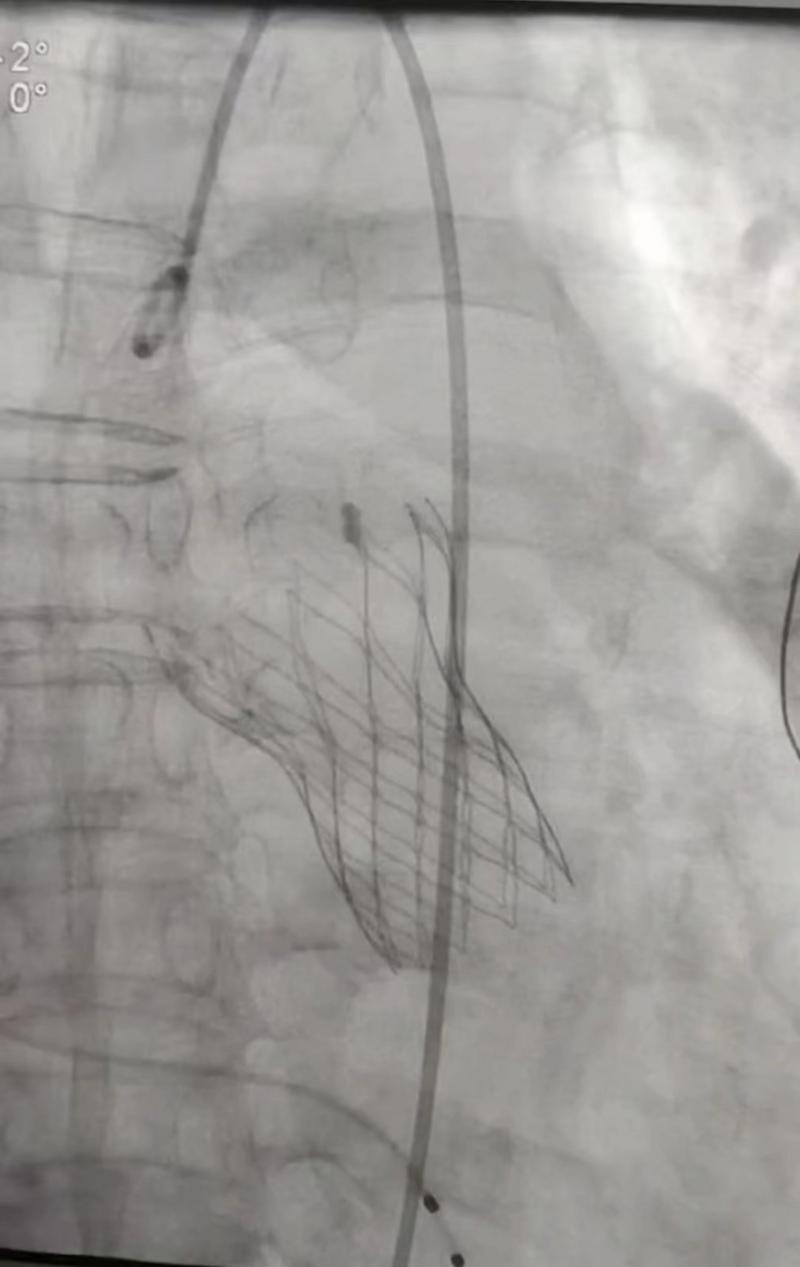

該患者因反復(fù)發(fā)作胸悶、氣喘、心前區(qū)疼痛入住市人民醫(yī)院心內(nèi)科,心臟超聲檢查發(fā)現(xiàn)主動(dòng)脈瓣嚴(yán)重返流伴升主動(dòng)脈夾層動(dòng)脈瘤,后經(jīng)大血管CTA檢查,證實(shí)超聲診斷,左竇上方有一破口,向上撕裂形成假腔。為預(yù)防病情進(jìn)一步加重,在心內(nèi)科主任王岳松的組織下,科室召開病例討論會(huì),研究下一步治療方案。討論結(jié)果一致認(rèn)為必須采取內(nèi)科介入或外科手術(shù)治療。由于患者年齡較大,兩種治療方案均存在較高風(fēng)險(xiǎn),外科開胸進(jìn)行主動(dòng)脈和升主動(dòng)脈置換,手術(shù)復(fù)雜且創(chuàng)傷大,風(fēng)險(xiǎn)更高;如果采取經(jīng)皮主動(dòng)脈瓣置換,創(chuàng)傷小、用時(shí)短,雖然術(shù)中有誘發(fā)夾層破裂的可能,但只要規(guī)范操作,總體風(fēng)險(xiǎn)可控。在告知患者及家屬兩種方案利弊后,患者及家屬選擇內(nèi)科經(jīng)皮瓣膜置換法。為慎重起見,心內(nèi)科團(tuán)隊(duì)再次組織全院相關(guān)科室及皖醫(yī)附院湯圣興教授線上交流討論,制定詳細(xì)的介入手術(shù)預(yù)案。介入手術(shù)當(dāng)天,在醫(yī)院麻醉手術(shù)科、ICU、胸心外科等相關(guān)科室配合下,心內(nèi)科團(tuán)隊(duì)在外院專家指導(dǎo)下,成功為該患者實(shí)施經(jīng)皮主動(dòng)脈瓣置換術(shù),手術(shù)非常順利,用時(shí)不到兩小時(shí),術(shù)后復(fù)查造影和心臟超聲,主動(dòng)脈瓣返流及主動(dòng)脈夾層基本消失,患者及家屬對(duì)醫(yī)院醫(yī)療技術(shù)和服務(wù)能力給予了很高評(píng)價(jià)。

成功置入經(jīng)皮主動(dòng)脈瓣